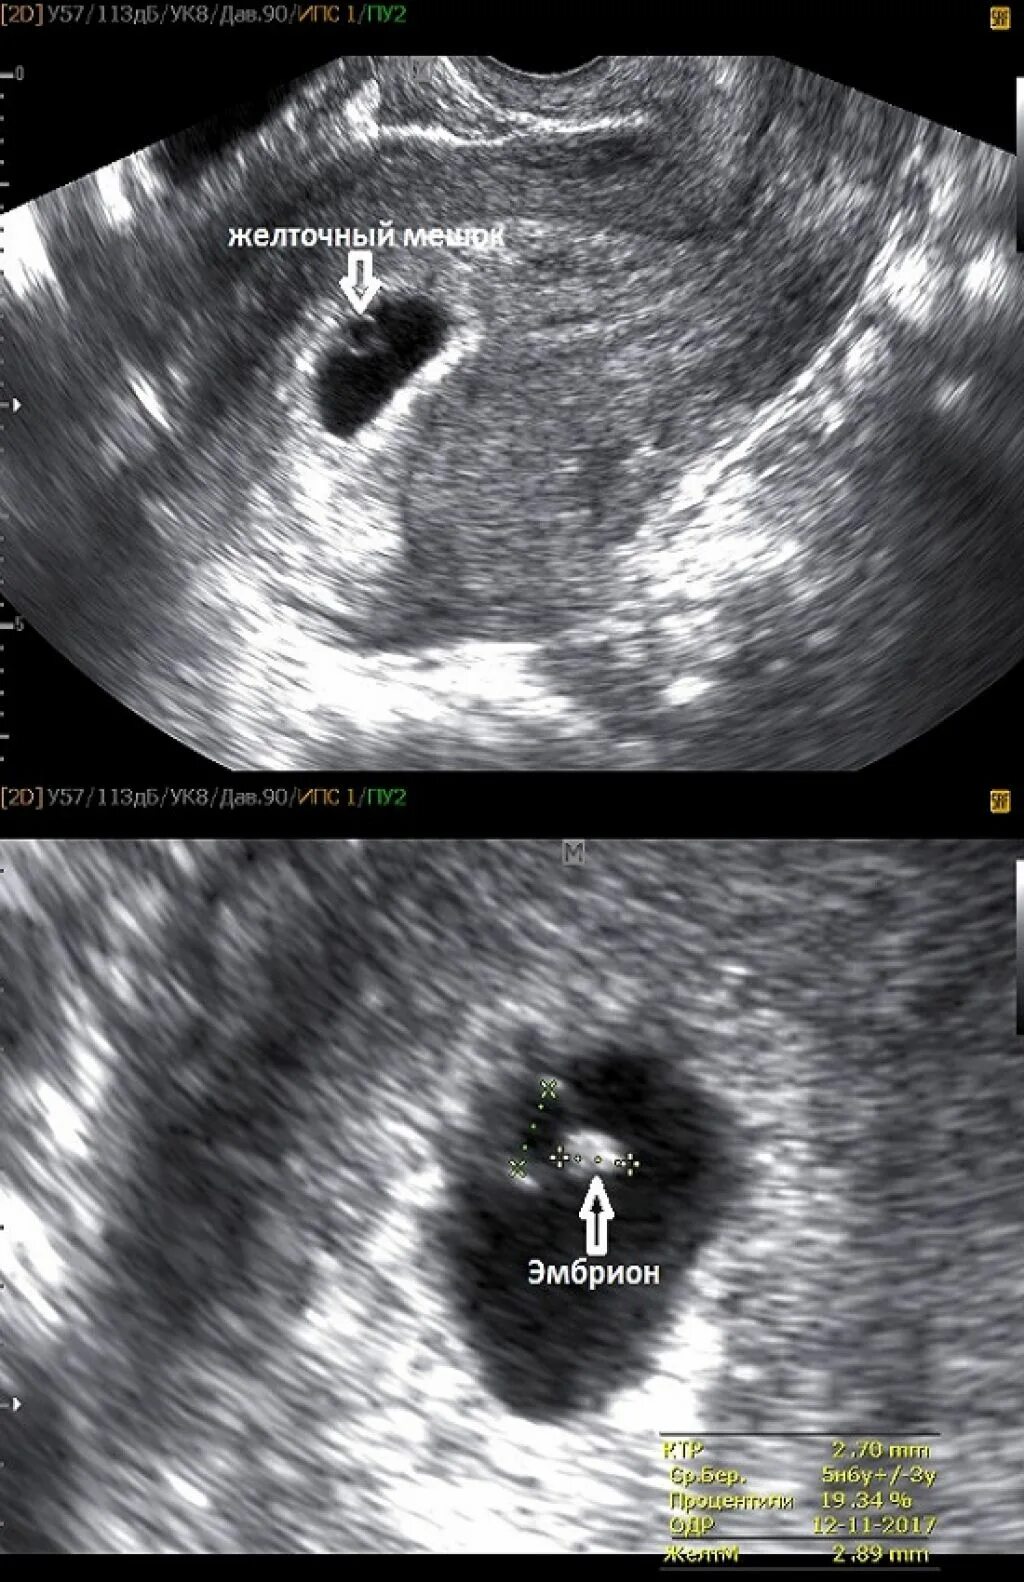

Узи 6 недель беременности желточный мешок. узи 8 недель беременности анэмбриония. плодное яйцо на 7 неделе беременности. плодное яйцо желточный мешок эмбрион.

Желточный мешок на 5 неделе беременности на узи. плодное яйцо 16мм,эмбрион 6мм. плодное яйцо 7 мм желточный мешок 4мм. плодное яйцо на 5-6 неделе беременности.

Плодное яйцо 16мм,эмбрион 6мм. анэмбриония 2 плодного яйца. неразвивающаяся беременность на ранних сроках узи. плодное яйцо 10 мм желточный мешок 4 мм.

Узи беременности 6-7 недель плодное яйцо. плодное яйцо на 7 неделе беременности. плодное яйцо с эмбрионом 7 недель. плодное яйцо 7 недель узи.

Плодное яйцо 8 мм желточный мешок 4 мм на 7 неделе беременности. узи 6 недель беременности желточный мешок. деформированное плодное яйцо на 7 неделе беременности узи. узи 9 недель беременности желточный мешок.